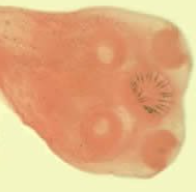

What is the species in this photo and WHY?

Taenia saginata and solium